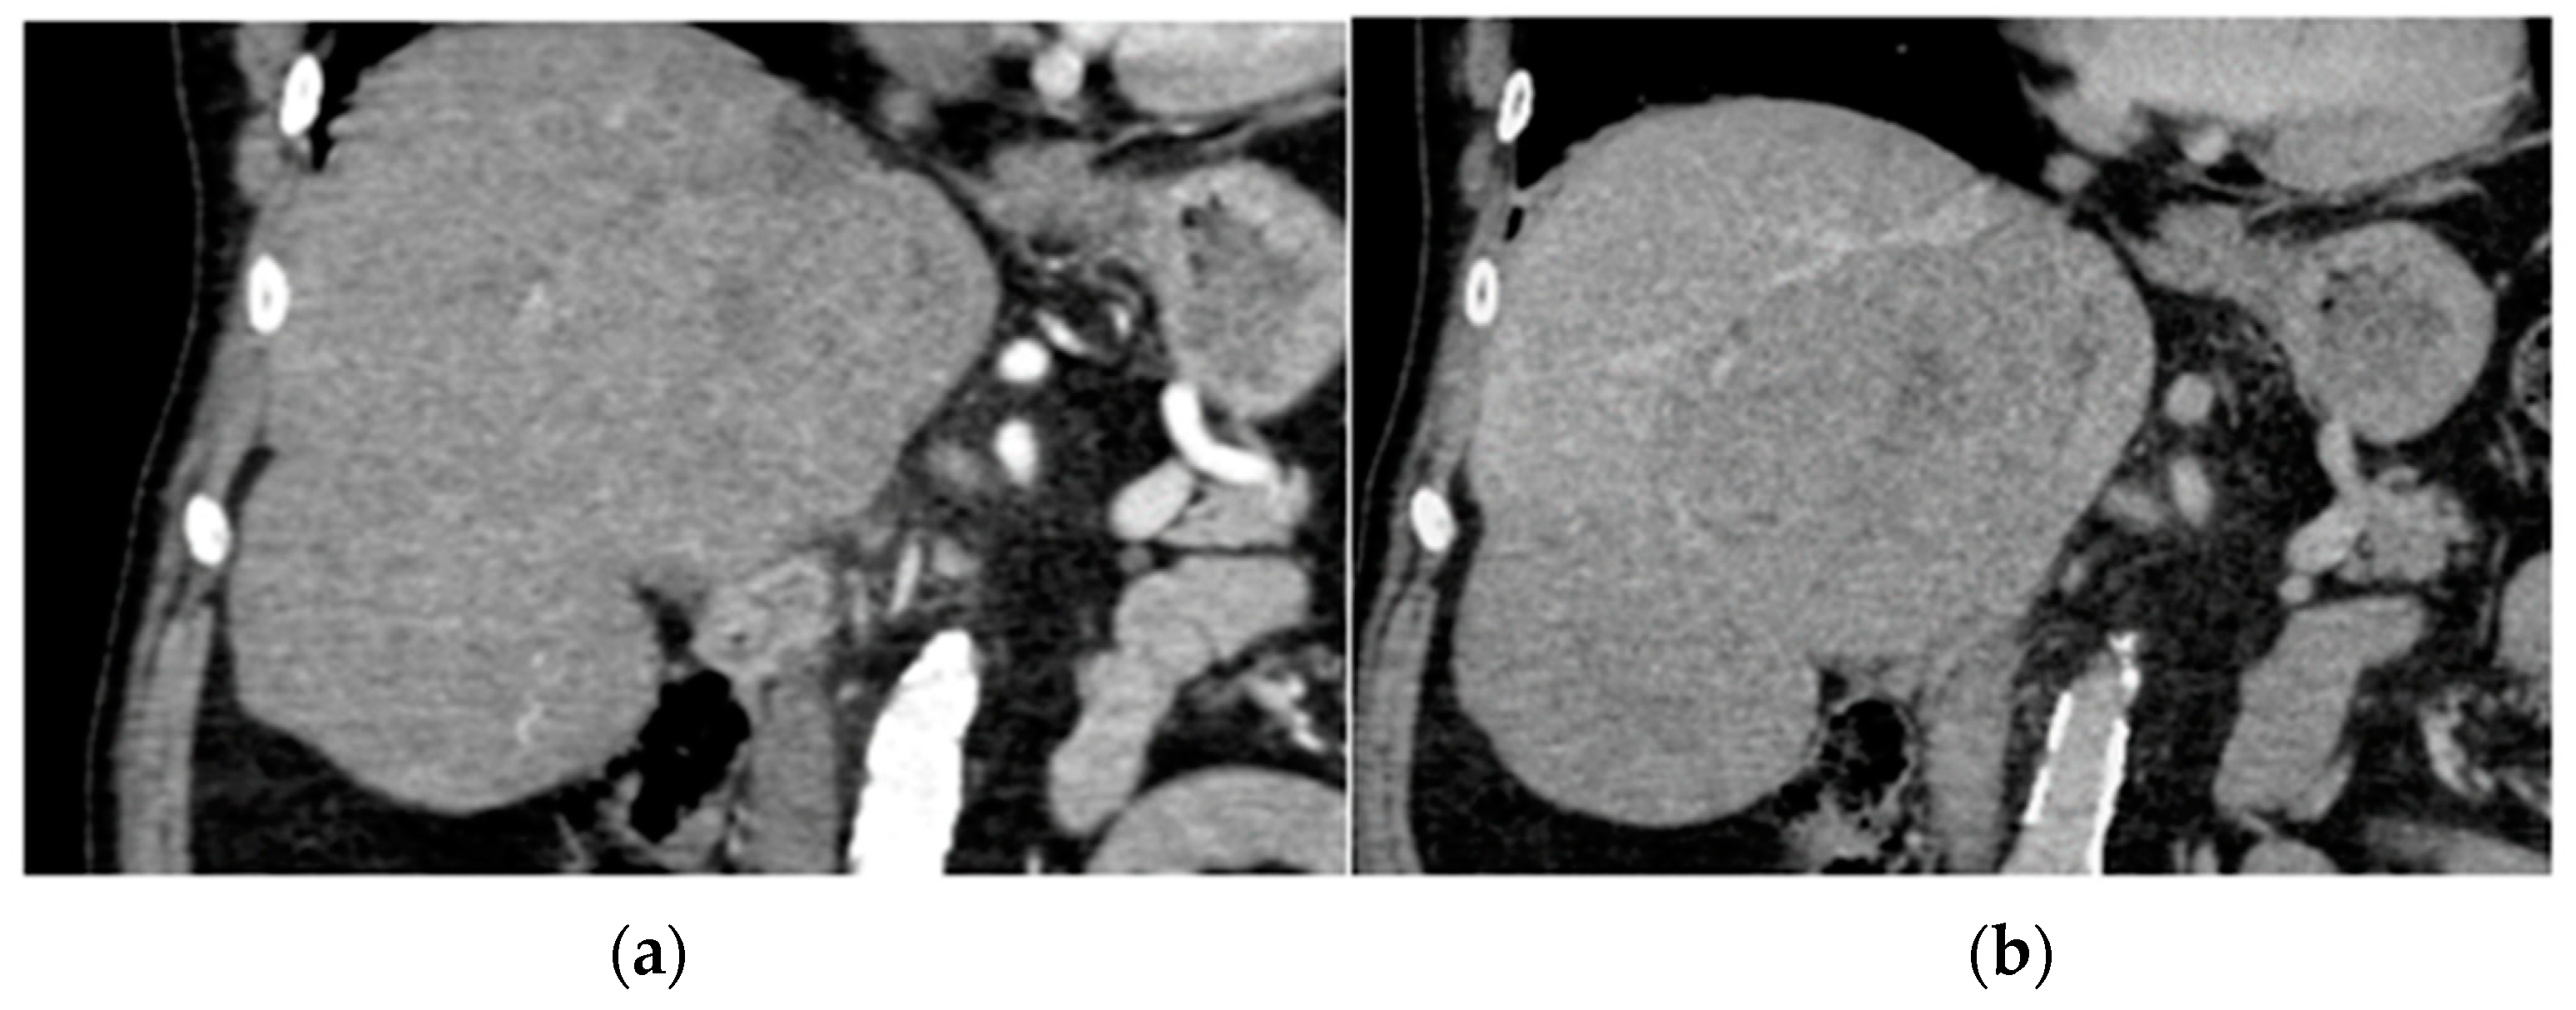

5. Liver